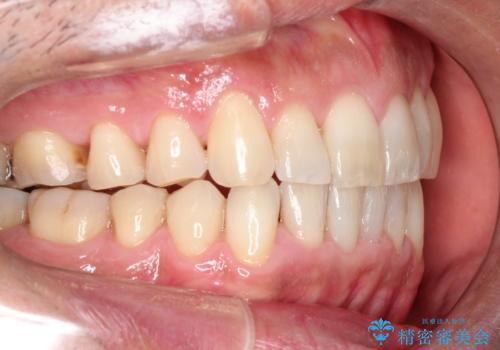

インビザライン invisalign ガタつきを治すマウスピース矯正

- 非抜歯・上顎臼歯遠心移動によるマウスピース矯正を計画した。

ガタつきを取り除くだけであれば非常に簡潔であるマウスピース矯正ですが、奥歯の位置関係の是正や、垂直的な歯の位置のコントロールなどが計画に含まれる場合、治療が難しくなってきます。